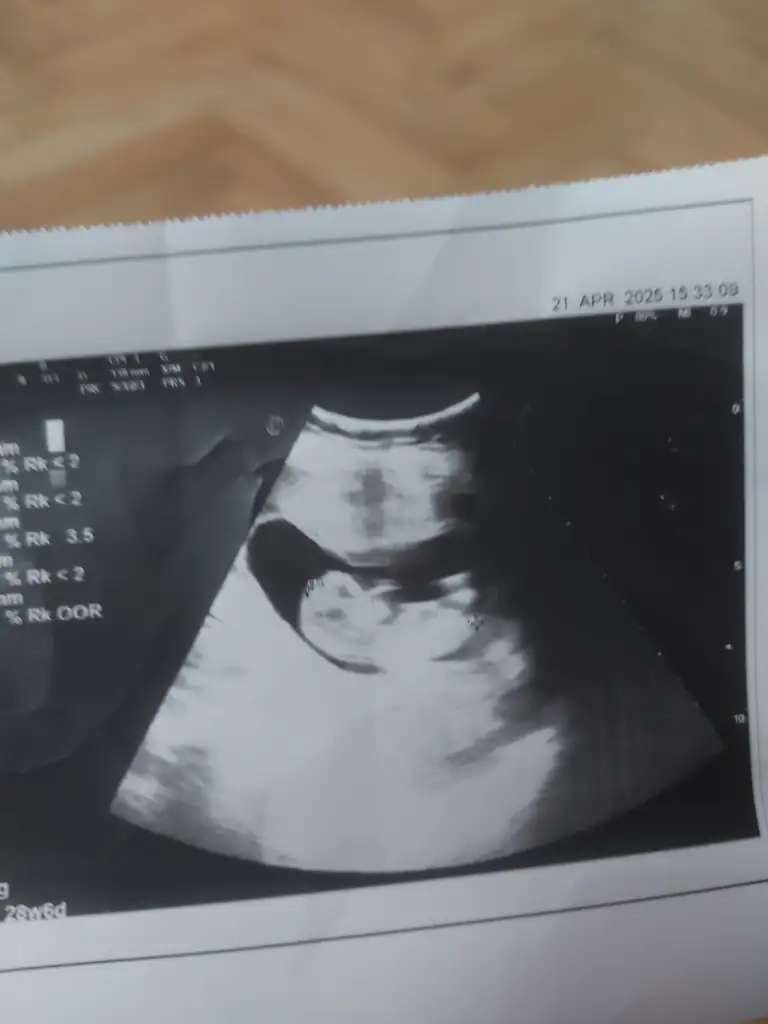

Benim içinde yorum yapabilirmisiniz arkadaşlar ilki 5.5haftalik ikincisi 12.haftalik...

• 20250422_181122.webp

14 KB · Görüntüleme: 69

• 20250422_053619.webp

13,3 KB · Görüntüleme: 66